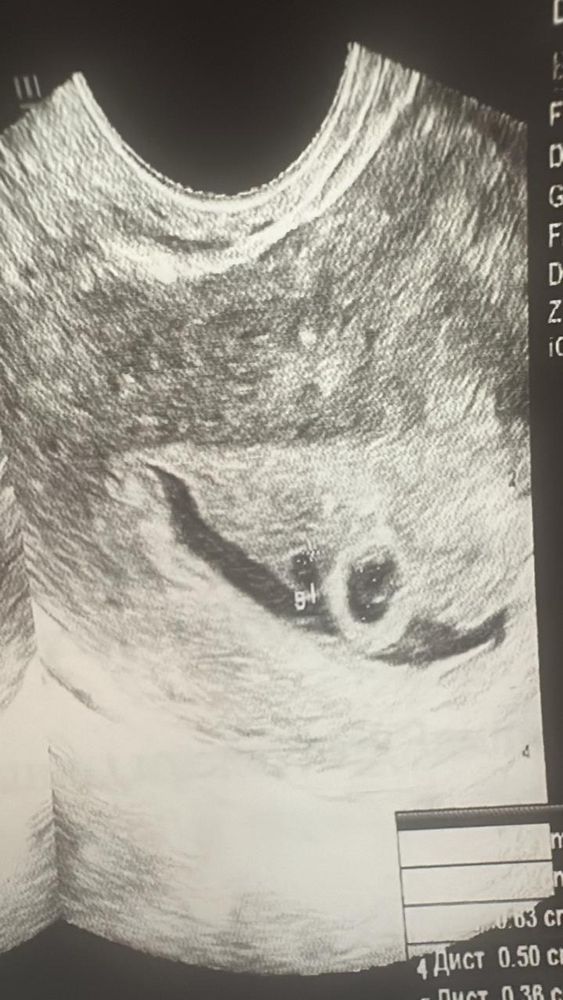

Здравствуйте. Я беременна. Первый день последних месячных до 10 го декабря 2024 года. Первый УЗИ 16.01.2025 года. Поставили срок 3-4 недели. Двойня под вопросом. И гематому с размером 18*3 мм. Повторный УЗИ 23.01.2025 двойную подтвердили. Но один меньше другого. И гематома выросла почти в два раза.

Обе УЗИ прикреплю